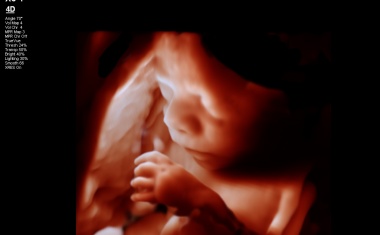

Mitte August 2023 sind in der Klinik für Geburtshilfe und Pränatalmedizin des Universitätsklinikums Hamburg-Eppendorf (UKE) verbundene Zwillinge auf die Welt gekommen.